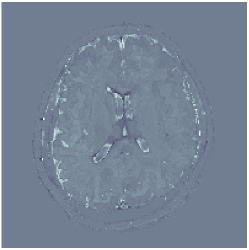

Two sets of experiments were conducted here: first, we used the 2D and 3D acquisition sequences for scanning a healthy volunteer’s brain (real-world acquisitions). Figures 6 and 7 display the parametric maps reconstructed from 2D spiral and radial readouts. We computed the T1, T2 and proton density (PD) maps using baseline reconstruction algorithms ZF, VS, LR, FLOR, AIR-MRF and our proposed LRTV. While baselines use DM either for quantitative inference or also during reconstruction (i.e. AIR-MRF), we further compare the DM-free LRTV’s performance when cascaded to DM, KM and MRFResnet for quantitative inference. For the 3D spiral acquisitions we compared LRTV and its closest competitor VS in Figure 8. Outcomes from other tested algorithm are displayed in the supplementary materials (Figure S5). Since FLOR does not use dimensionality-reduction, our system ran out of memory during 3D reconstruction; hence results are not reported in this case.

VI-E1 Discussion

The LRTV-DM and LRTV-MRFResnet perform on par, and both outperform all tested baselines for reconstructing T1, T2 and PD maps in all acquisition schemes. This can be observed both visually in Figures 6, 7, 8, S2 and S3, and quantitatively in Table IV across all tested metrics. Other baselines were unable to successfully remove the under-sampling artefacts in TSMIs, and these errors propagated to the parameter inference phase and resulted in inaccurate maps. Temporal-only priors incorporated within LR are shown insufficient to regularise the inverse problem and LR sometimes (e.g. 2D spiral acquisitions) can admit solutions with even stronger artefacts than the model-free ZF baseline. This issue was previously studied for other non-Cartesian MRF readouts that similar to our spiral/radial trajectories, miss to sample the corners of the k-space in all timeframes (see section 2.2.2 and figure 2 in [19]). In the absence of reference for the k-space corners information, the LR iterations despite minimising the objective can converge to solutions with high-frequency artefacts, as visible in the computed maps. This highlights the need for adding an appropriate spatial-domain regularisation. FLOR reduces the LR’s artefacts but this improvement is limited because the suggested nuclear norm penalty does not incorporate an explicit spatial regularisation. Further for reducing artefacts, FLOR can introduce an undesirable bias in the computed T1/T2 maps e.g. see error maps in Figures S2 and S3. The non model-based VS baseline incorporates spatial regularisation and results in spatially smoother maps than ZF and LR, but it is unable to output artefact-free images. Further and consistent with our in-vitro experiment, we observe that VS overestimates the T2 values (e.g. in White and Grey matter regions) in tested 2D acquisitions i.e. the spatial regularisation trades off agains the quantification accuracy. The model-based AIR-MRF adds spatial regularisation through 2D/3D low-pass Gaussian filters however this trades off the sharpness of the computed maps and can increase the errors at the tissue boundaries (we searched Gaussian spreads that keep the blurs and high-frequency artefacts minimal). For our acquisition readouts, Gaussian filters performed better than disk filters of [19] for avoiding strong Gibbs artefacts. On the other hand, the spatiotemporally regularised LRTV greatly improves the TSMI reconstructions i.e. 4 dB enhancement compared to the closest competitor baseline (Table IV). This enables computing accurate and aliased-free multi-parametric inference using DM or the DM-free learning-based alternative MRFResnet as visible in Figures 6, 7, 8, S2 and S3. MRResnet and DM score competitive quantitative inference results i.e. T1 and T2 MAPE less than 5% and 9%, respectively (Table IV). KM also outputs comparably accurate T1 maps, however this shallow learning model despite having a model size larger than MRFResnet, is unable to learn accurate T2/PD quantification and it results in poor estimated maps, consistent with our observations in section VI-C.